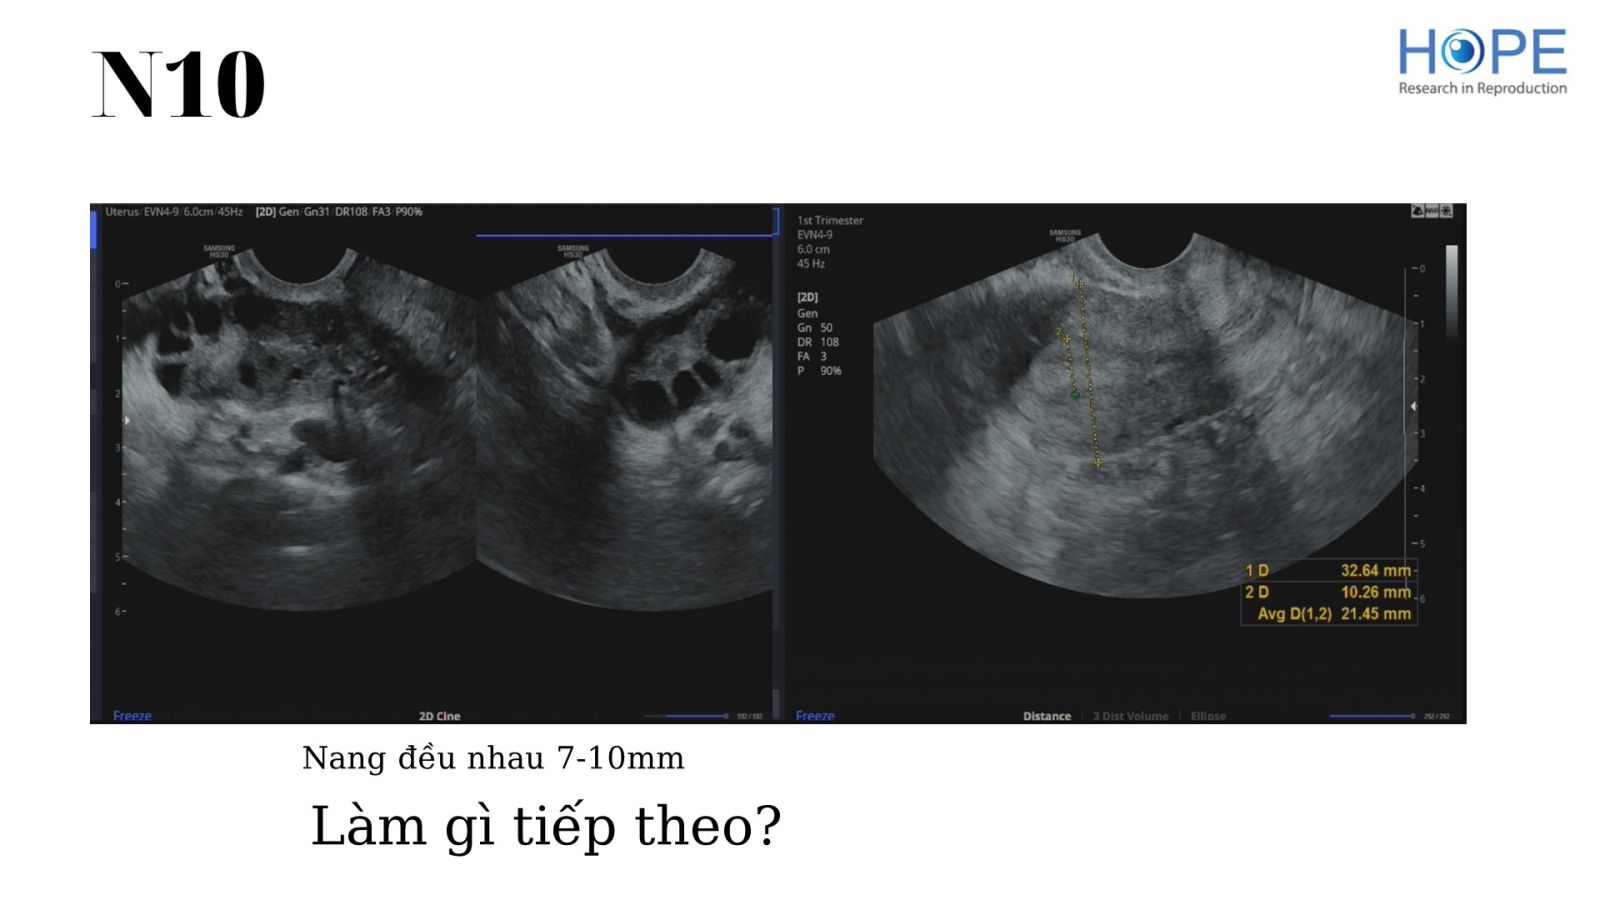

Các phác đồ kích thích buồng trứng nhẹ để IUI –  cách theo dõi kích thích buồng trứng

BS Lê Thị Hà Xuyên - IVFMD Phú Nhuận